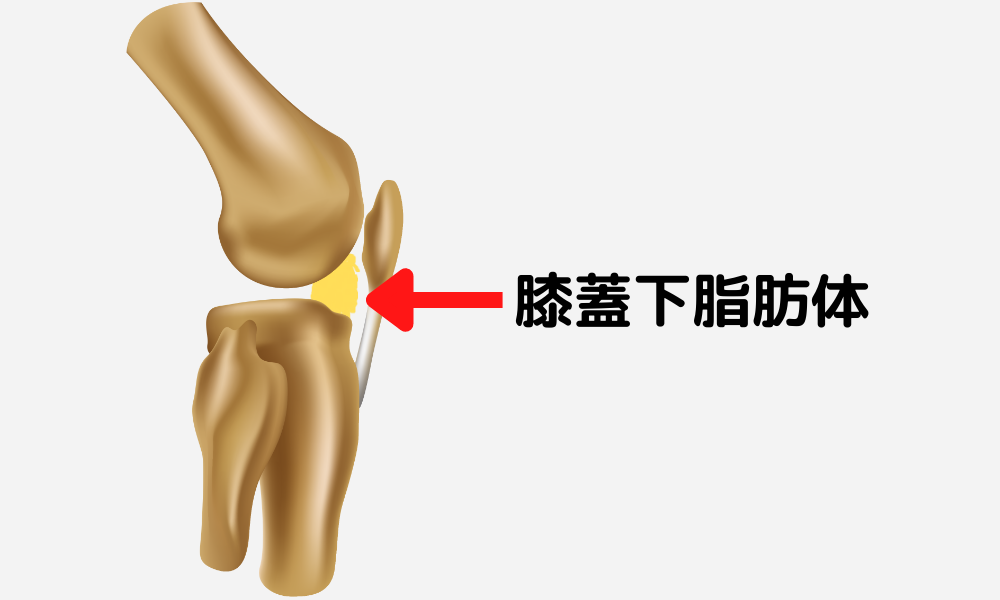

身体のバランスが崩れて身体の様々な痛みが生じます。関節の痛みの正体が脂肪体や筋肉であることは以前の記事で紹介しました。

詳しくはこちらの記事「【関節の痛みの正体】軟骨や変形は関係ない!?実は脂肪体だった!!」をご参照下さい。

医師の弱点として脂肪体や筋肉が問題となっている場合の痛みの対応が挙げられます。

実は関節の痛みで最も問題となる脂肪体や筋肉の問題はレントゲンにもCTにもMRIにも写らない事がほとんどです(肉離れや血腫は写る)。

関節の痛みに対して医師の診察上、命に関わる病気や手術等といった外科的な治療が必要な所見が無ければ、鎮痛剤や簡単なストレッチや運動療法等を処方されて経過観察となる事が多く、根本的に脂肪体や筋肉に対する問題を解決出来ない事が非常に多いです。